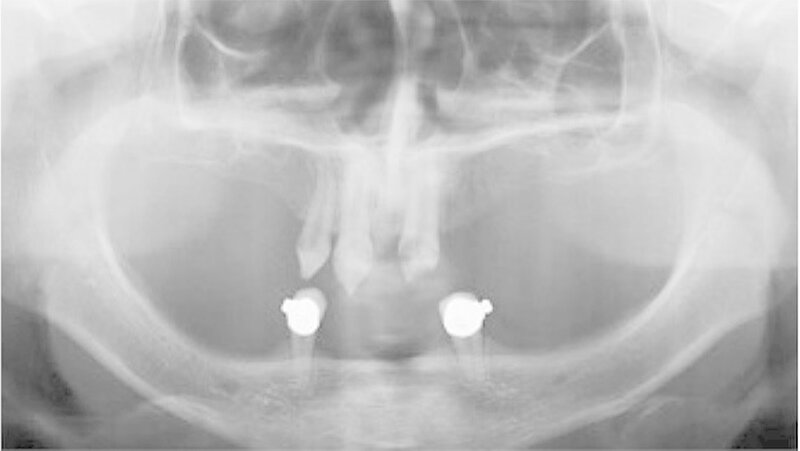

Der bei Behandlungsbeginn 14-jährige Patient war mit einer neun beziehungsweise fünfjährigen Prothese im Unter- beziehungsweise Oberkiefer versorgt (Abb. 2 und 3). Die angelegten Zapfenzähne 12, 11 und 21 waren bereits mehrfach konservierend restauriert und wiesen diverse Stellen mit Sekundärkaries auf. Die Kronenränder der Zähne 33 und 43 waren deutlich sondierbar. Der Kieferkamm im Unterkiefer war aufgrund der fehlenden Zahnanlagen sehr schmal (Abb. 4 bis 6). Die Panoramaschichtaufnahme zeigte das reduzierte vertikale Knochenangebot (Abb. 7). Da die Vitalerhaltung der wenigen Restzähne aufgrund des jungen Alters des Patienten unbedingt anzustreben war, wurde als Behandlungsziel im Ober- und Unterkiefer eine Versorgung mit Hybridprothesen, retiniert auf Teleskopkronen, festgelegt.

Bei dieser bei Behandlungsbeginn 16-jährigen Patientin waren seit Geburt nur die beiden ersten Molaren im Oberkiefer ausgebildet. Die Folge waren schmale und niedrige Alveolarkämme mit einem flachen Gaumengewölbe (Abb. 16 und 17). Die röntgenologische Abbildung bestätigte das geringe vertikale Knochenangebot. Eine Formanomalie der Zahnwurzeln ließ auf taurodonte Molaren schließen. Beide Molaren wiesen ausgedehnte kariöse Läsionen auf (Abb. 18).